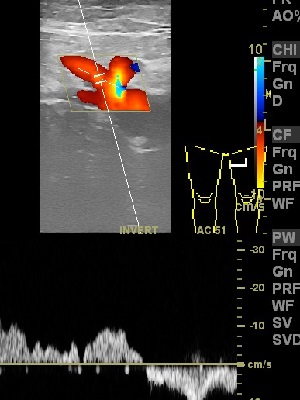

Sprawdzany jest też kierunek przepływu w poszerzonych perforatorach aby ocenić stopień ich uszkodzenia w przebiegu przewlekłej niewydolności żylnej.

Najczęściej jest to tylko poszerzenie nadpowięziowego odcinka perforatorów wskutek podwyższonego ciśnienia w żylakach ale kierunek przepływu pozostaje prawidłowy do żył głębokich.

Jednak czasami po przebytej nieleczonej zakrzepicy żył głębokich zdarza się przepływ wsteczny w perforatorach to znaczy od głębokich do powierzchownych.

Jest to skutek uszkodzenia głębszego odcinka perforatora przez zakrzep lub stan zapalny.